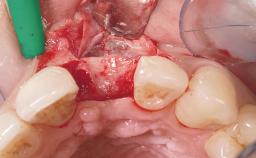

A 36-year-old female patient was referred for the replacement of the upper left central incisor (tooth 21), which had fractured. Although the tooth had been asymptomatic for many years, the crown began to loosen, at which time she presented to her dentist for an assessment. Teeth 21 and 22 had both been endodontically treated many years previously. She was a healthy individual and a non-smoker.

On examination, the patient had a low lip line and only displayed the coronal half of the anterior teeth when smiling.